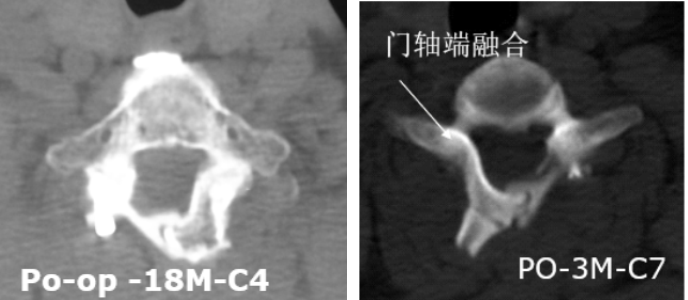

3.有效防止术后再关门,为脊髓提供强力保护